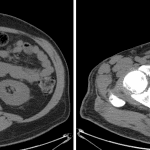

Ultrasound